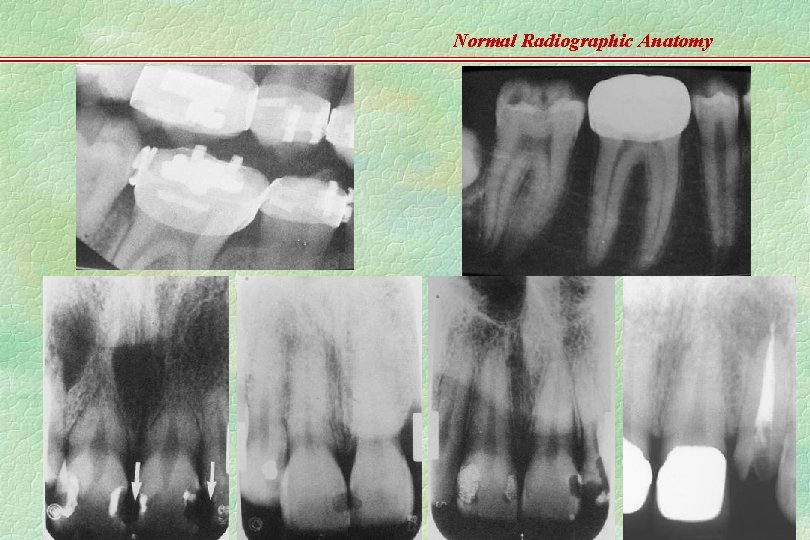

Normal Radiographic Anatomy Developing tooth WWC

Normal Radiographic Anatomy SUPPORTING STRUCTURE u Lamina dura u Alveolar crest u Periodontal ligament space u Cancellous bone WWC

Normal Radiographic Anatomy SUPPORTING STRUCTURE Lamina dura u u Thin R-O (radiopaque) shadow bounding the sound tooth socket Wider & more dense in teeth of heavy occlusion WWC

Normal Radiographic Anatomy Alveolar crest u u u R-O line between teeth, gingival margin of the alveolar process, cortical border of the alveolar bone. A point of bone in ant. teeth ; flat in post. CEJ to alveolar crest. . . < 1. 5 mm Recede apically with age Markable resorption with periodontal disease Continuing with lamina dura and forms a sharp angle → Rounding angle indicative periodontal disease WWC

Normal Radiographic Anatomy RESTORATIVE MATERIALS u u u Complete R-O : silver amalgam, gold, silver points R-O : stainless steel pins, calcium hydroxide base , gutta-percha stainless steel crown, orthodontic appliance R-L : silicates, composite , porcelain WWC